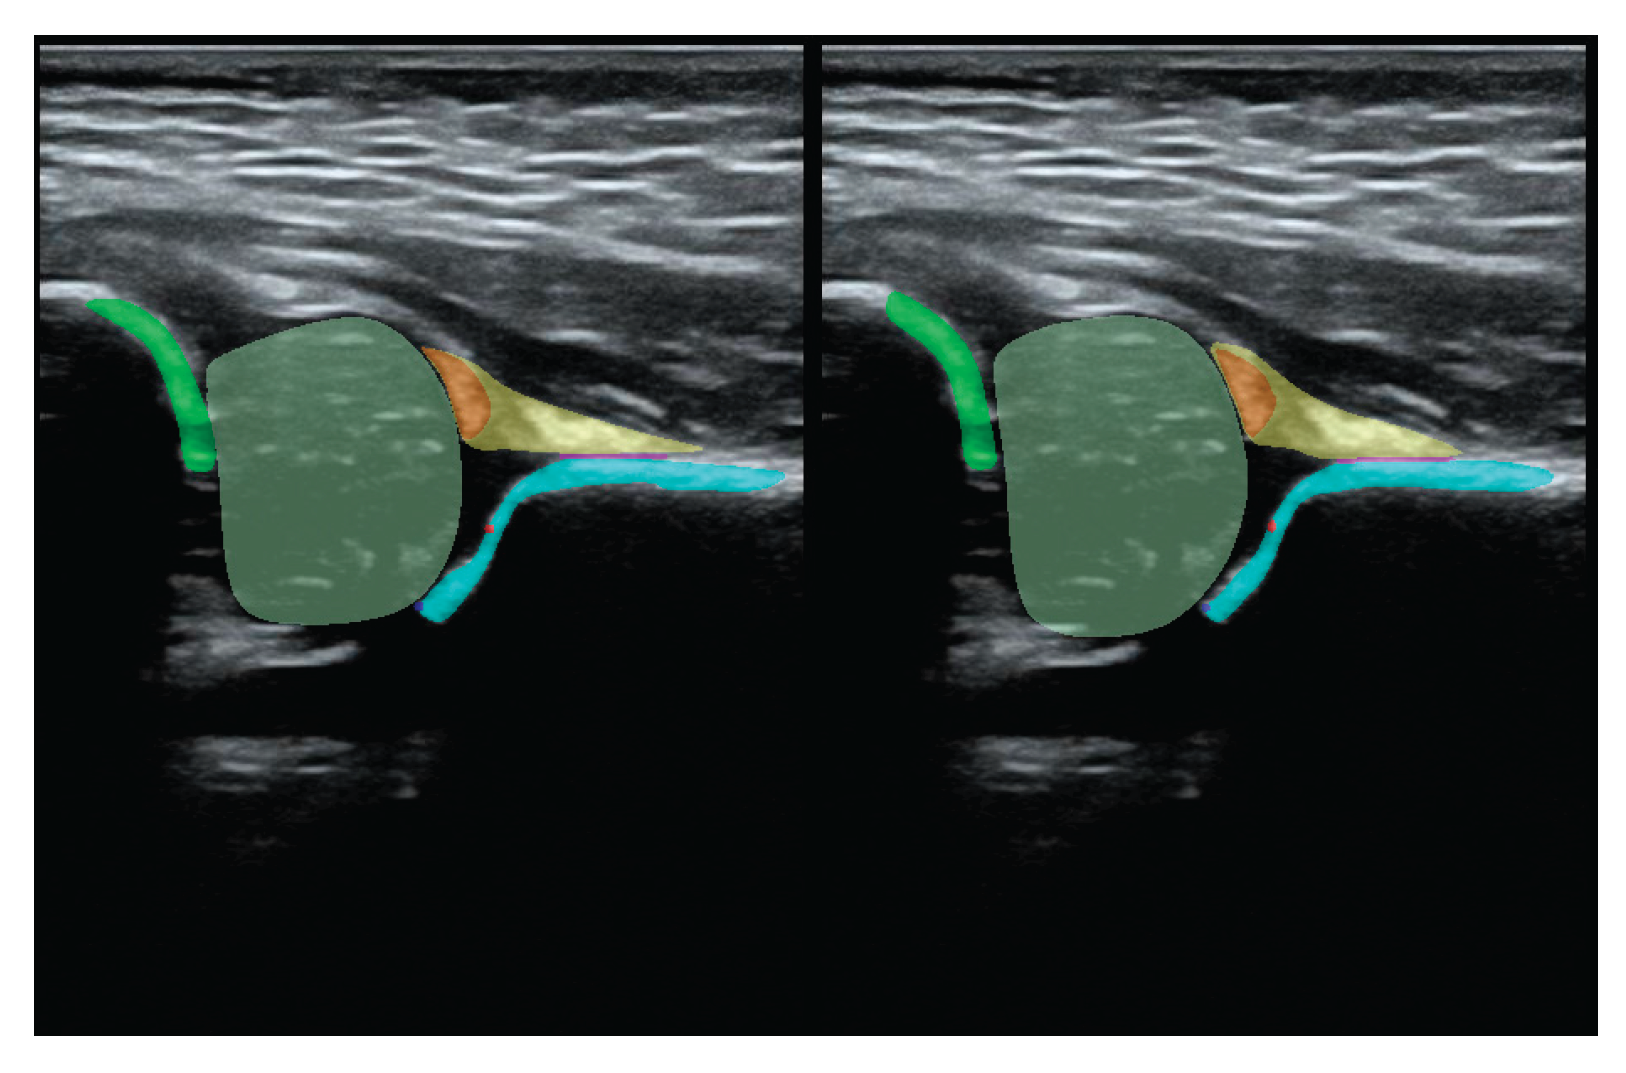

Additionally, during the model training process, the PaddleSeg library uses various pre-processing techniques (e.g. Resize, Normalize) and augmentation techniques (e.g. RandomHorizontalFlip, RandomDistort), which were also used in our training. The first step of pre-processing involved cropping the images to the ultrasound area to eliminate regions that do not pertain directly to the ultrasound scan. The second step involved the preparation of masks containing only 5 classes (chondro-osseous border, femoral head, labrum, cartilaginous roof and bony roof). This step was performed to create the input for Model-5 (Figure 2).

Figure 2. Result of pre-processing: extracting the USG area from the image and preparing masks for Model-5 (lower picture) and Model-8 (upper picture).